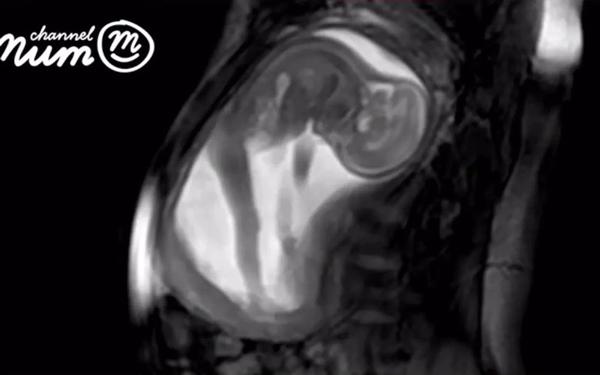

Trong đoạn video kéo dài 20 giây, hình ảnh thai nhi đang nghịch dây rốn, xoay đầu từ bên này sang bên kia, co duỗi người được thể hiện khá rõ nét. Ở những giây kết thúc, em bé thậm chí còn co người đạp mẹ một cái khá mạnh khiến bụng biến dạng.

Bé co người đẩy mẹ méo bụng.

Video trên được thực hiện nhờ các thuật toán máy tính ghi lại hình ảnh từng chuyển động nhỏ của em bé trong quá trình siêu âm. Thông thường, nếu khi siêu âm, em bé chuyển động quá nhiều và nhanh thì hình ảnh sẽ không sử dụng được. Với việc siêu âm "đa đầu dò" mới, các biến chứng sẽ dễ dàng được phát hiện hơn.